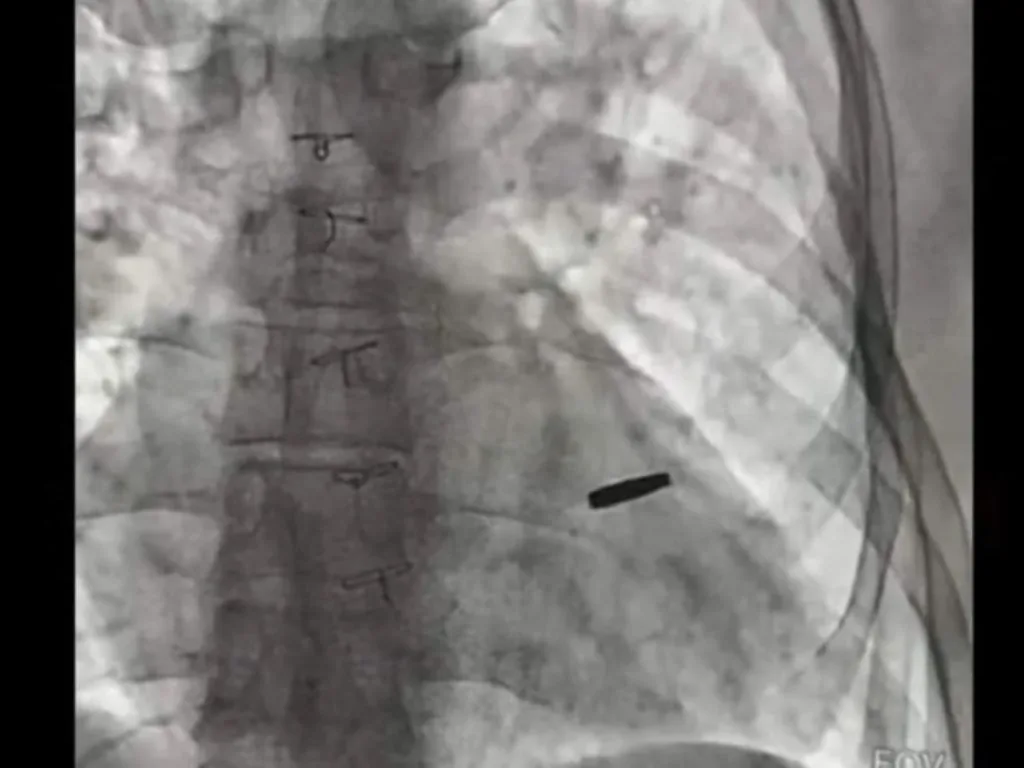

З серця звільненого з полону захисника «Азовсталі» дістали кулю, з якою він прожив 3 роки

З серця звільненого з російського полону українського військового дістали кулю, з якою він прожив три роки.

Поранений військовий захищав «Азовсталь» і потрапив до полону під час атаки на Маріуполь. Три роки він був у неволі, а два місяці тому його обміняли.

«Три роки він був з цієї кулею, прожив. На щастя, вона нічого не пошкодила, зараз ми її видалили, пощастило хлопцю», — наголосив Тодуров.